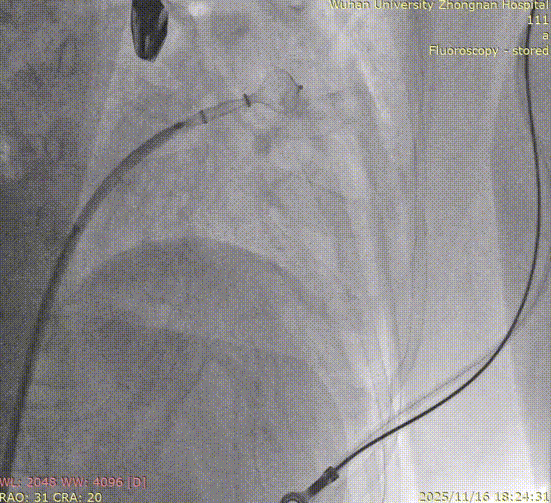

Left Atrial Appendage Closure (LAAC):The delivery system was successfully advanced into the left atrium. Precise measurements of the LAA orifice and depth were taken under multi-angle TEE and DSA guidance. Given the LAA's large orifice (nearly 34mm), conical cauliflower shape, and shallow usable depth, a LACBES2434 occluder was selected. Using the "extreme coin technique," the closure was successfully achieved.

DSA